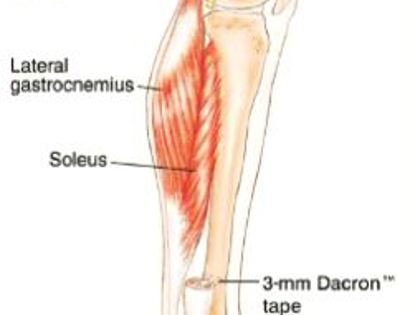

Removal of tumor and reconstruction. Reconstruction of the defect (space where fibula was removed) involves muscle flaps utilizing the gastrocnemius muscle (calf muscle) to cover the tibia (shinbone).

Using sutures, the gastrocnemius is secured to soleus muscle (lower leg muscle) and knee joint to provide adequate coverage.